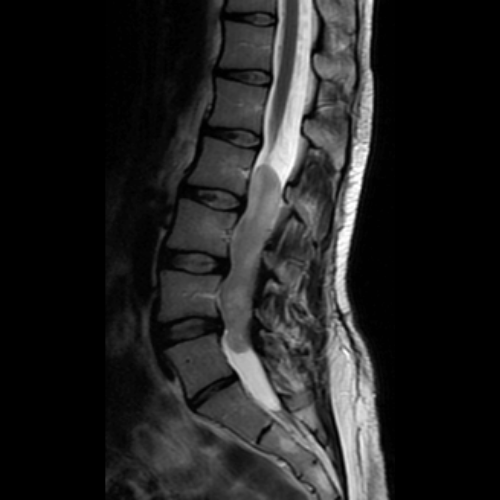

Chiari malformasyonu (yaygın adıyla Chiari sendromu), beyincik (serebellum) dokusunun kafatasının altındaki açıklıktan (foramen magnum) omurilik kanalına doğru sarkmasıyla karakterize yapısal bir bozukluktur. Normal şartlarda tamamen kafatası içerisinde yer alması gereken beyincik parçaları, kafatasının bu bölgedeki hacminin yetersiz olması veya şekil bozukluğu nedeniyle aşağı doğru itilir. Bu durum, hem beyin sapı ve omurilik üzerinde fiziksel bir baskı oluşturur hem de beyin omurilik sıvısının (BOS) doğal akışını engelleyerek merkezi sinir sistemi üzerinde çeşitli baskılara yol açar.

Belirtiler genellikle çocukluk veya genç yetişkinlik döneminde fark edilir ve kişiden kişiye büyük farklılıklar gösterir. En karakteristik semptom, özellikle öksürme, hapşırma, ıkınma veya başı aniden hareket ettirme gibi durumlarda şiddetlenen ense ve baş ağrısıdır. Bunun yanı sıra hastalarda denge kaybı, el becerilerinde azalma, kollarda ve bacaklarda uyuşma, yutma güçlüğü, görme bozuklukları ve uyku apnesi gibi nörolojik şikayetler gözlemlenebilir. Birçok vaka, başka bir nedenle çekilen MR (Emar) görüntülemeleri sırasında tesadüfen teşhis edilmektedir.

Tedavi süreci, semptomların şiddetine ve hastanın yaşam kalitesine olan etkisine göre planlanır. Ancak şiddetli ağrıların, belirli nörolojik defisitlerin veya sinir sistemi hasarı riskinin bulunduğu durumlarda cerrahi müdahale temel çözüm yoludur. "Posterior fossa dekompresyonu" adı verilen cerrahi işlemle kafatası tabanındaki basınç azaltılır, beyincik için daha fazla alan yaratılır ve beyin omurilik sıvısının normal akışı yeniden sağlanır. Erken teşhis, sinir sisteminde oluşabilecek kalıcı hasarların önlenmesi açısından kritik önem taşır.